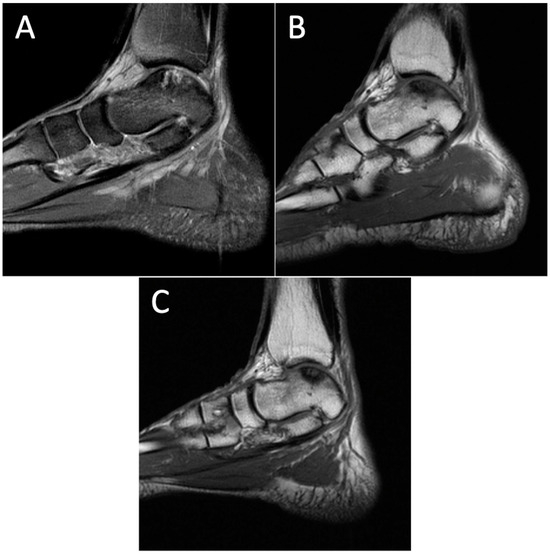

Figure 3.

Degenerative progression of the left medial osteochondral lesion outlined in red on sagittal MRIs from 2009 to 2021. The timeline of lesion progression includes MRI scans from 2009 (A), 2011 (B), 2016 (C), 2017 (D), 2018 (E), 2019 (F), and 2021 (G). This sagittal view demonstrates the osteoarthritic progression of the lesion from 12.2 mm × 10.4 mm in 2009 to 18.4 mm × 15.3 mm in 2021.